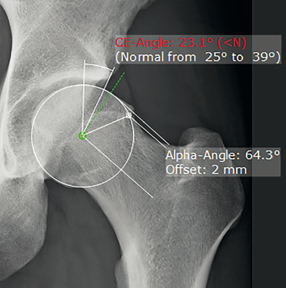

4. Đo đạc và đánh giá hình thái giải phẫu khớp háng một cách chuyên nghiệp với chức năng phân tích hội chứng "F.A.I"

Để nghiên cứu mối liên quan giữa các đặc điểm hình thái tổng thể của hông và phạm vi chuyển động ở những bệnh nhân có tật và những bệnh nhân không có triệu chứng (những bệnh nhân khỏe mạnh có các đặc điểm chụp X quang đặc trưng cho FAI).